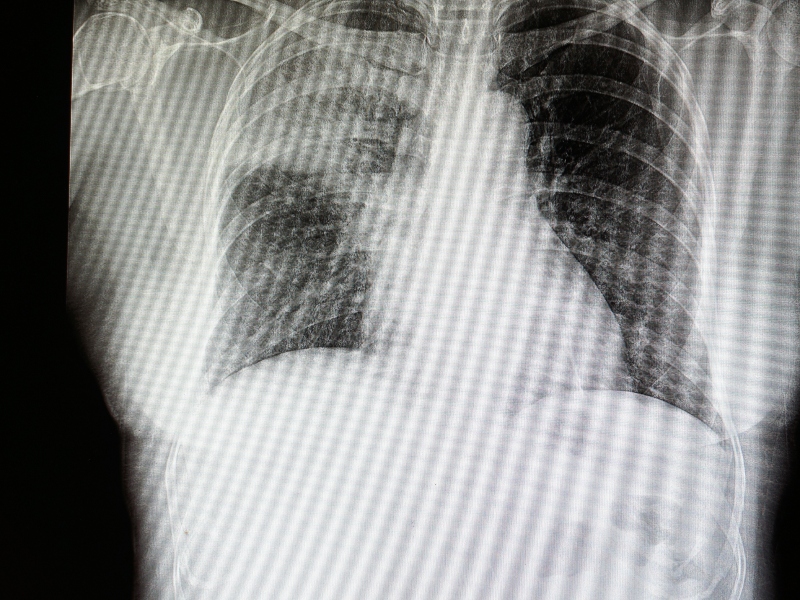

التهاب رئوي جرثومي هو التهاب في الرئتين نتيجة عدوى جرثومية، وتوجد أنواع مختلفة من الجراثيم التي يمكن أن تُسبب الالتهاب الرئوي، ويمكن أن يحدث هذا النوع من الالتهاب الرئوي في كلا الرئتين أو رئة واحدة أو جزء من الرئة.